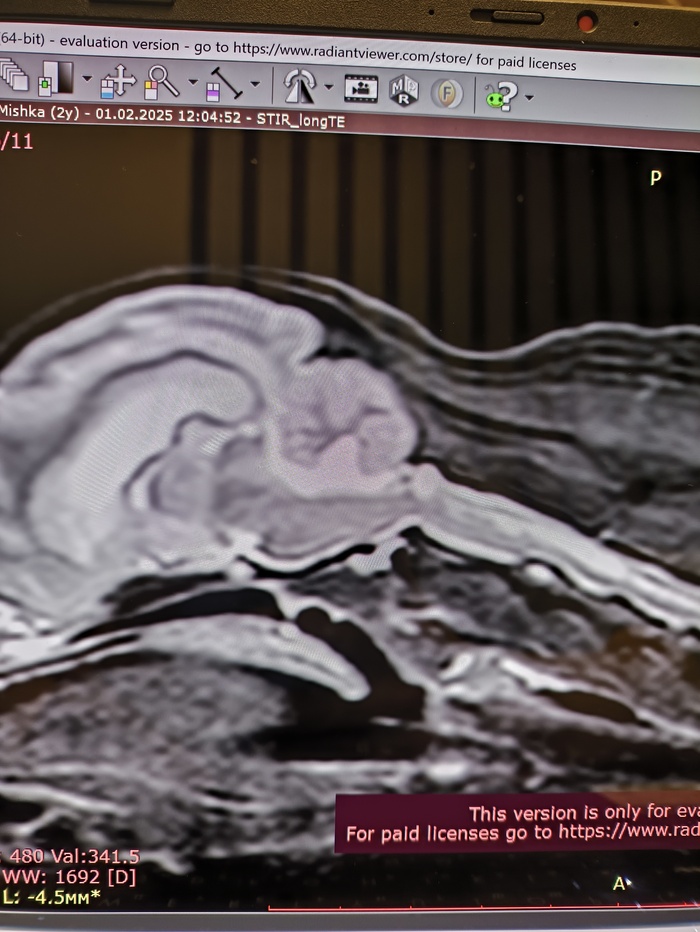

Киари синдром у собаки, сирингомиелия. Нужен совет

Всем привет. Есть собака (шпиц 3года, 3 кг). У него подозревают Киари-синдром, сирингомиелию. Сделали ему мрт.

В шейном отделе признаки дегенеративно-дистрофических изменений межпозвонковых дисков. Признаки сирингомиелии, отека спинного мозга по типу пресирингса на уровне сегмента С5-С7.

Голова: признаки краниоцервикальной мальформации, признаки вентрикуломегалии, признаки частично-пустого турецкого седла.

Очень интересно, нормальное ли положение мозжечка или нет. Виден ли Киари синдром или нет?

На следующей неделе я веду его на прием, но ветеринар уже говорил про операцию.